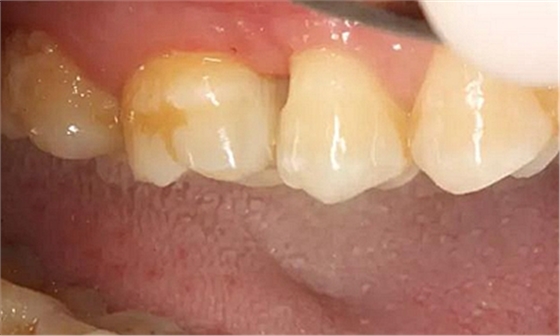

患者男性,35歲,B6銀汞充填后食物嵌塞,要求重新充填,口內(nèi)檢查見B6近中鄰頜面銀汞充填物,局部缺損,有繼發(fā)齲,去除原充填物及繼發(fā)齲,發(fā)現(xiàn)齲壞位于牙齦下方,給予冠延長手術(shù),同期嵌體預(yù)備,后一次性取模。(同樣設(shè)計為齦上邊緣)

硅橡膠取模后,灌注模型,科爾琥珀樹脂制作嵌體。

一周后拆線,口內(nèi)試戴合適,粘結(jié)嵌體。